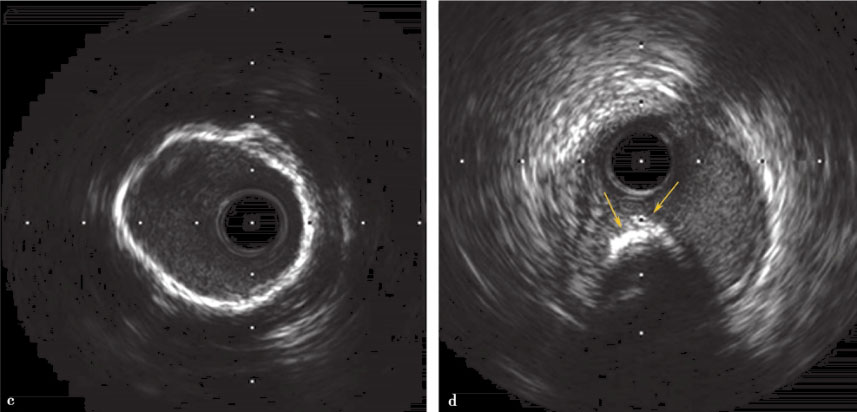

文末有福利|90后小伙血管状况不如90岁老人,跑步晕倒住进icu_超声

图片尺寸793x638